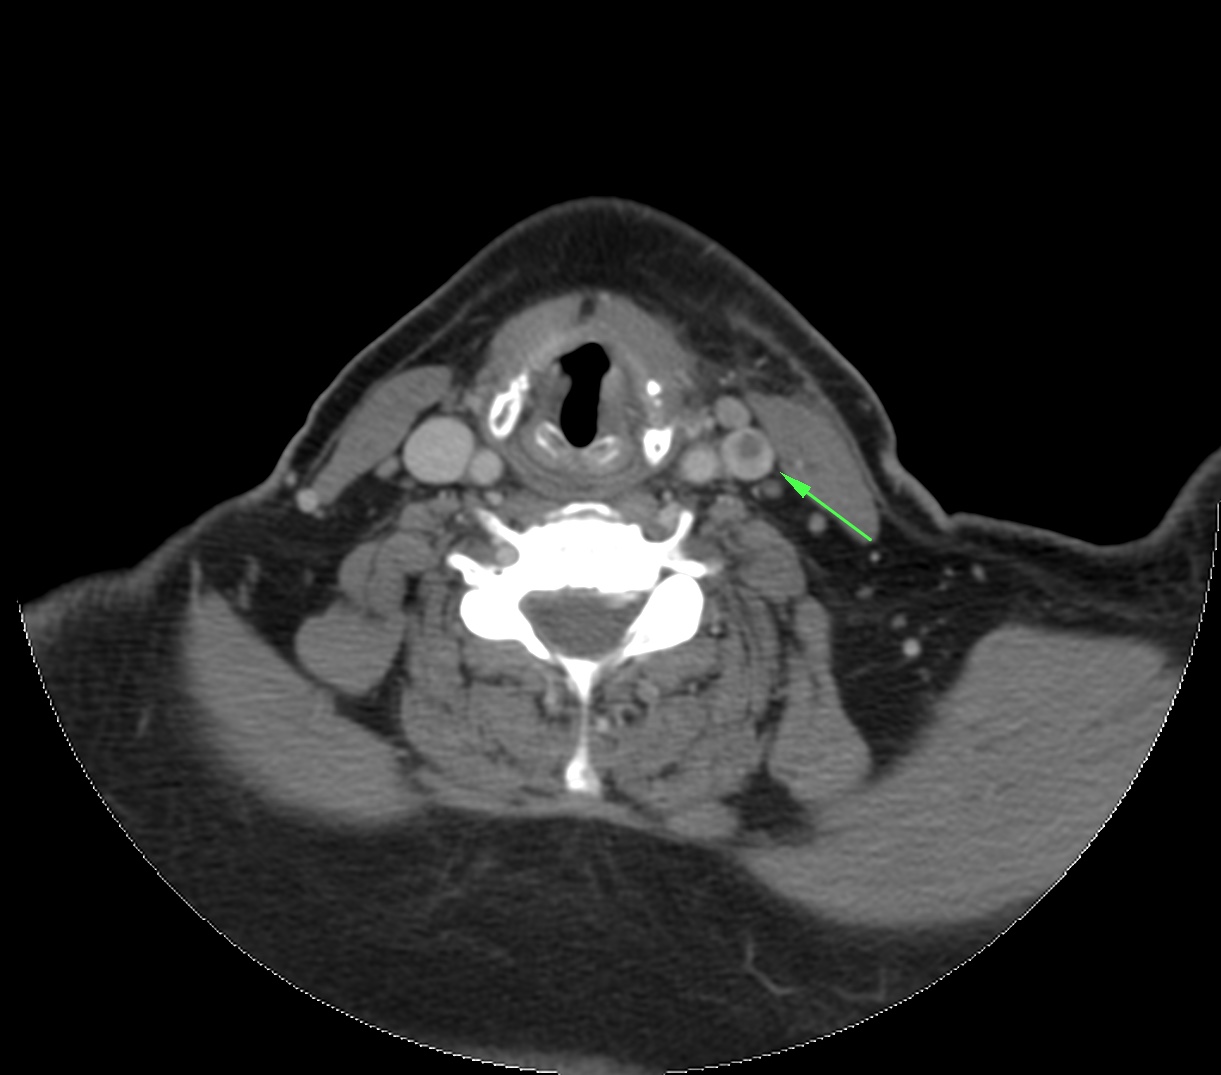

Síndrome de Lemierre: Tras una infección de la orofaringe, se produce tromboflebitis de vasos de cuello. Suelen ser infecciones asociadas con comobilidades tales como cirugía o radioterapia.

- Los defectos de repleción en la TC con contraste indican trombosis.

- La afectación de la grasa perivascular indica proceso inflamatorio.

- Si hay afectación de la vena yugular interna, existe alto riesgo de migración de émbolos sépticos a los pulmones. Por tanto, dada la gravedad, es fundamental realizar además una TC de tórax y es el radiólogo el que debe sugerir o establecer el diagnóstico de la enfermedad en un primer momento.